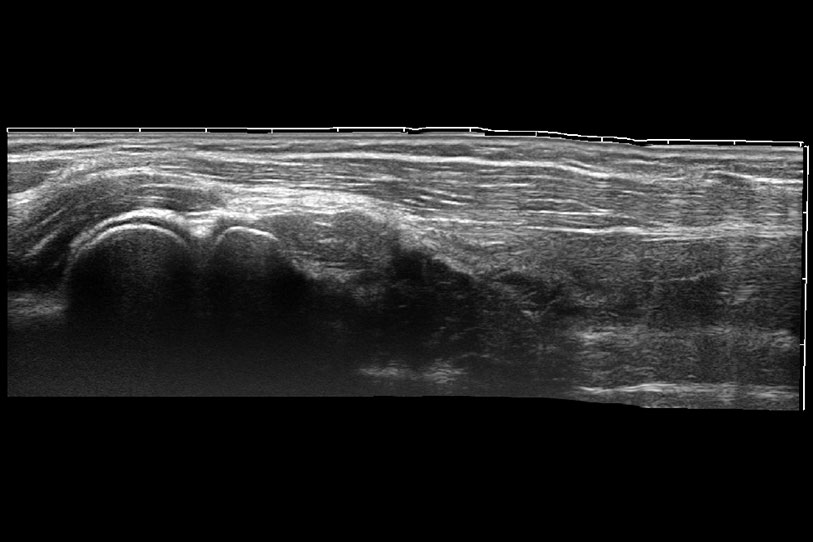

ProPet 70 進(jìn)一步提升了微米成像算法,更加注重對基礎(chǔ)原始圖像的還原和保留,在有效減少斑點(diǎn)噪聲、增強(qiáng)組織邊界顯示的同時(shí),避免過度優(yōu)化丟失真實(shí)的解剖信息。

通過色彩血流和實(shí)時(shí)寬景相結(jié)合,可觀察到完整的靜脈或動脈的血流,方便醫(yī)生檢查。實(shí)時(shí)掃查過程中,如有任何操作失誤也可以很容易地進(jìn)行回掃擦除,而不會中斷掃查。

為精細(xì)結(jié)構(gòu)及組織邊緣提供高清晰度的圖像和更大的成像視野。幫助減輕醫(yī)生的用眼疲勞,快速精準(zhǔn)獲得測量的數(shù)據(jù)。